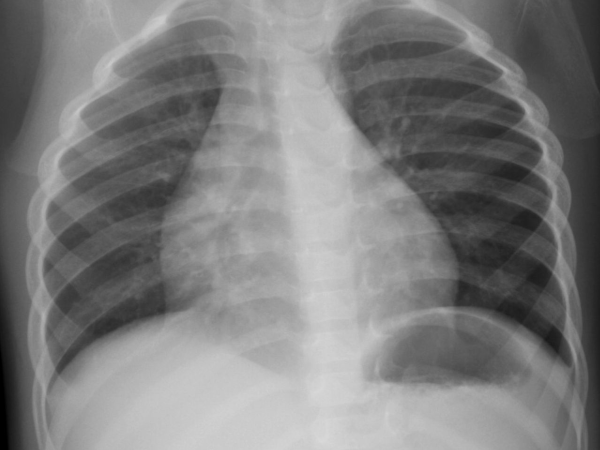

Egy tüdő röntgen során a páciens a modern készülékekkel kb. 0,1 mSv dózist kap, de egy modern PET-CT vizsgálat során 20 mSv-nél nagyobb dózist is kaphat, terápiás kezelésnél pedig lokálisan ugyan, de akár több mint 3 nagyságrenddel nagyobb értéket.